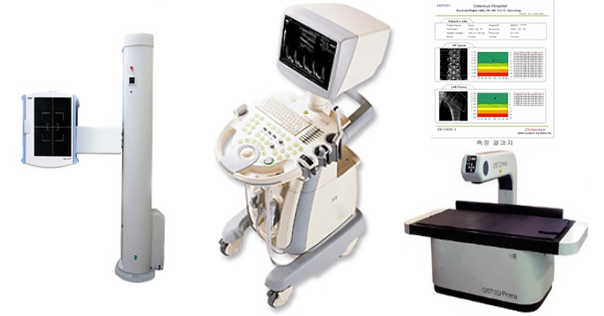

본원에서는 디지털 방식에 의한 일반방사선 촬영 및 초음파 검사, 전신 골다공증 검사기를 통한 FULL PASS 시스템 쉽게 골절 및 골다공증의 병변을 실시간으로 확인

할 수 있습니다.

본원에서는 병적 골절 예방읠 위하여 X-선 흡수계측법(DEXA)에 의한 전신골밀도 측정기를 도입 운영중에 있으며 경미한 외상에도 골절 되기 쉬운

요추부 및 고관절등의 7부위를 측정할 수 있는 최신 시스템을 갖추고 있습니다.